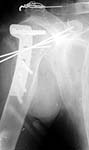

A man 47 y.o. just admitted to our unit with the fracture of proximal humerus and posterior luxation of the head. 1 month since the injury.

He was operated through extended anterior approach. Luxation of the head was reduced, the tubercle was found already united to the head. Few small fragments were removed. Transarticluar wires for 4 weeks, plaster cast to 8 weeks are planned. See attachment for images.